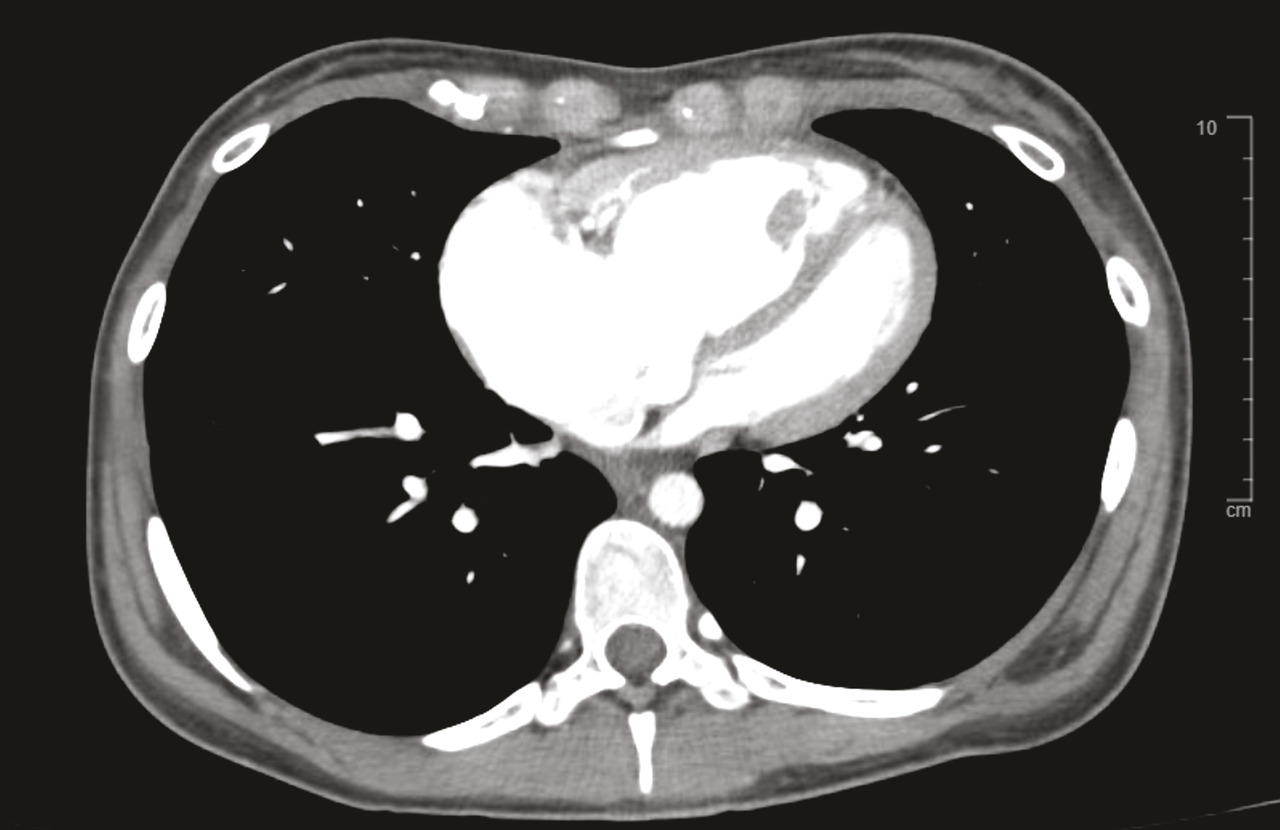

Le scanner thoracique en coupes millimétriques permet de rechercher des éléments évocateurs de maladie veino-occlusive pulmonaire (épaississement des septa, nodules flous en verre dépoli, adénopathies médiastinales) ou d’une pathologie respiratoire sous-jacente (emphysème, pneumopathie interstitielle diffuse…) [fig. 4 et 5].1,2Un angioscanner thoracique est indispensable pour le bilan d’opérabilité des patients atteints d’HTP-TEC.

L’injection de produit de contraste au temps artériel pulmonaire (angio-TDM thoracique) permet de rechercher des lésions thromboemboliques chroniques.